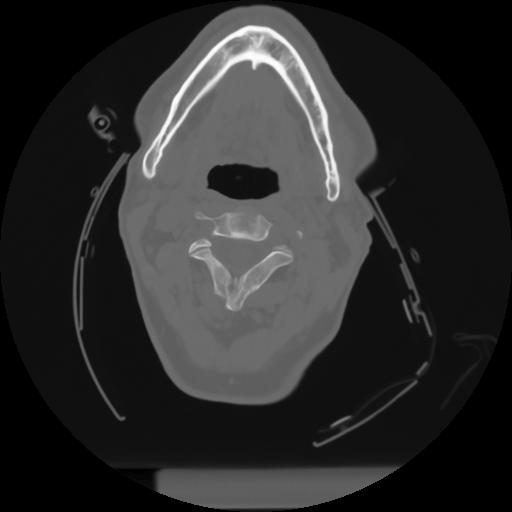

10 P.BLANDAS,,Axial,2.0,P.BLANDAS,,